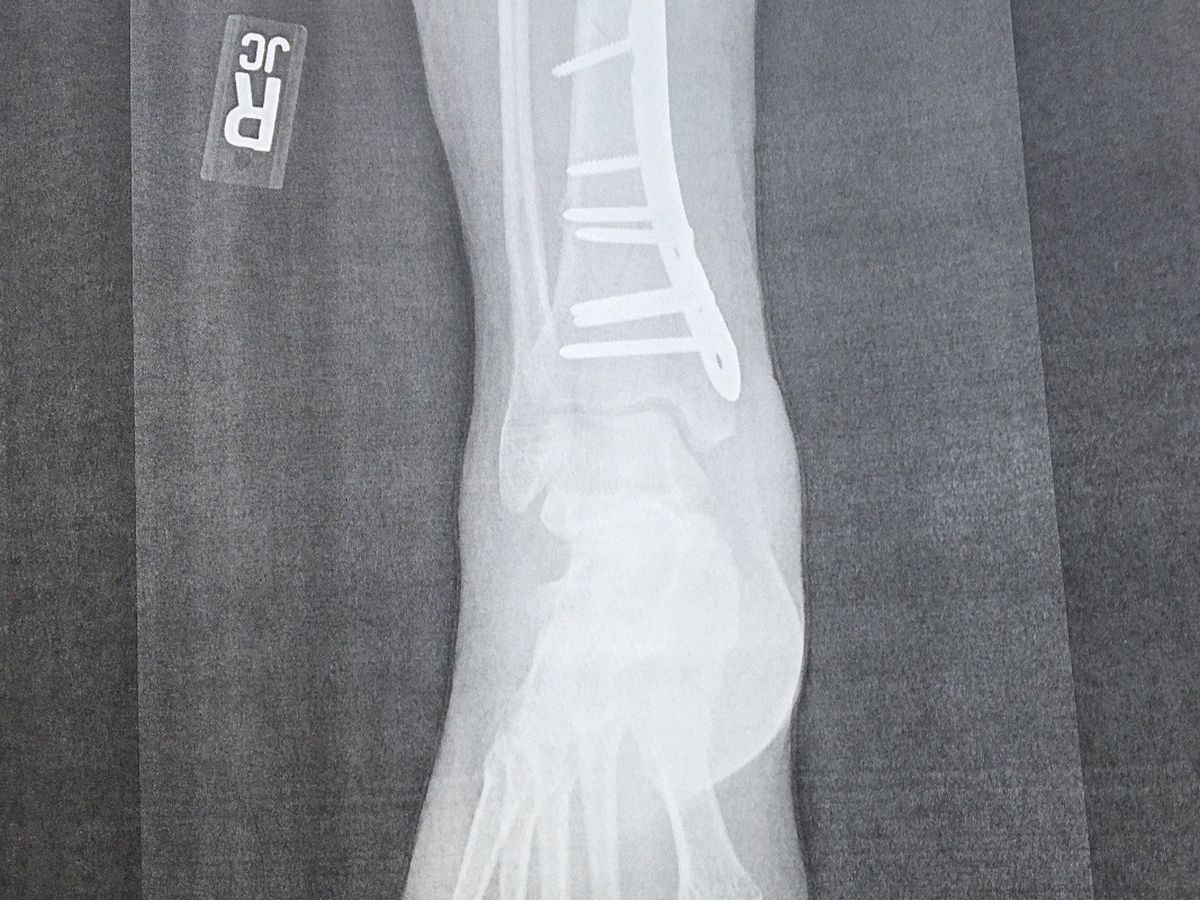

In September of 2019, Jessica was riding her new dirtbike, Tina, on a family trip when she had an unfortunate fall that fractured her tibia/fibula. If you know anything about medicine, you know that Jessica did a *really* good job on this injury.

Since then, Jessica has had several surgeries, the most recent scheduled for today to clean out a bone infection. She has been placed on significant work restrictions, and her employer has been overall unable to accommodate her light duty. She has run out of medical leave compensation though she continues to amass medical bills, including very expensive monthly COBRA payments. Though always very responsible with her money, her reserves have run out.